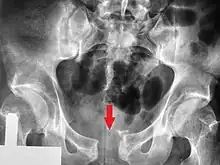

A pelvic X-ray showing an open book fracture

Open book fracture

One specific kind of pelvic fracture is known as an 'open book' fracture. This is often the result of a heavy impact to the groin (pubis), a common motorcycling accident injury. In this kind of injury, the left and right halves of the pelvis are separated at front and rear, the front opening more than the rear, i.e. like an open book that falls to the ground and splits in the middle. Depending on the severity, this may require surgical reconstruction before rehabilitation.[11] Forces from an anterior or posterior direction, like head-on car accidents, usually cause external rotation of the hemipelvis, an “open-book” injury. Open fractures have an increased risk of infection and hemorrhaging from vessel injury, leading to higher mortality.[12]